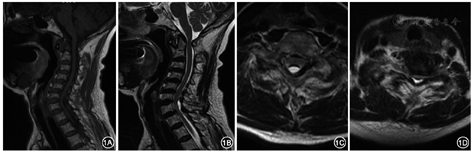

女性,66岁,因"行走不稳7年,双下肢麻木无力加重1周"于2018年6月8日入院。患者7年前无明显诱因出现行走不稳,转身困难;1周前出现双下肢麻木、无力,不能行走,双上肢无明显症状,无明显排便、排尿困难或大小便失禁,无鞍区麻木、晨僵,无关节红肿、发热畏寒等,否认既往头颈部外伤史。患者症状持续不缓解,遂于我院就诊。体检:右侧肋弓以下痛觉减退,左侧胸骨角平面以下痛触觉减退,双下肢位置觉消失,会阴部痛触觉减退不明显,两侧上肢肩外展、屈伸肘、伸腕、握拳及小指外展肌力均为Ⅴ级,两下肢屈髋、伸膝、足背伸、踇背伸及跖屈肌力Ⅱ级,双上肢肌张力无明显增高或降低,两下肢肌张力稍增高,双侧肱二头肌腱反射(++),双侧肱三头肌腱反射(++),双侧膝腱反射(+++),肛门反射(+),双侧Hoffmann征阴性,双侧Babinski征阳性。脊柱MRI检查结果示:颈椎生理曲度反弓,颈椎退行性改变,寰齿关节前间隙增宽,寰枢椎脱位,压迫相应颈髓;C7椎体向前滑移;C6~T1水平黄韧带区域占位性病变,呈T1WI低信号、T2WI高信号,考虑囊肿,椎管狭窄,相应颈髓受压、信号增高(图1)。脊柱CT平扫示:占位性病变内可见散在点状钙化。颈椎动力位X线片示:寰枢椎明显不稳。过伸位X线片示:寰枢椎脱位可复位(图2)。实验室检查:类风湿因子、抗溶血链球菌O、免疫球蛋白(IgG、IgM、IgA)、补体C3及C4、抗核抗体、抗中性粒细胞胞质抗体均呈阴性,血尿酸未见明显异常。诊断:(1)退行性寰枢椎脱位(可复性);(2)C6~T1水平椎管内硬膜外占位:黄韧带囊肿?(3)C7椎体滑移Ⅰ度;(4)不完全截瘫。因患者同时存在退行性寰枢椎脱位与C6~T1水平椎管内占位,均对颈脊髓造成明显压迫,考虑患者不完全截瘫由C6~T1水平椎管内占位所致可能性较大,但不能完全排除寰枢椎脱位影响,故于2018年6月19日在全身麻醉下行"颈后路寰枢椎脱位切开复位,椎弓根螺钉内固定术"及"颈后路C6~T1水平椎板切除及椎管减压,椎管内硬膜外占位切除,椎弓根螺钉内固定术"。术中在切除病变水平椎板后发现此处黄韧带增厚明显,可见囊肿样病变组织位于黄韧带内,被黄韧带包裹,压迫脊髓,椎管明显狭窄,病变与邻近小关节间无接触及交通。术中小心地从硬膜外剥离并完整切除病变组织及周围黄韧带,此过程中增厚的黄韧带与硬膜囊无明显粘连。体外切开病变组织见其内含凝胶样黏液,囊壁与黄韧带粘连紧密,较难分离,提示病变组织起源自黄韧带。术后复查X线片及CT可见颈椎内固定稳固,寰枢椎脱位已复位,C6~T1水平椎管减压充分(图3)。术后病理学检查示:镜下见纤维组织增生,胶原变性,部分区呈囊壁样结构,散在钙盐沉浸,并见少量软骨组织,未见滑膜层,未见异型细胞、尿酸盐沉积。病理学诊断为黄韧带囊肿(图4)。术后2周患者可在搀扶下站立;术后3个月可在搀扶下行走,但步态不稳,双下肢麻木较前有所好转;术后6个月可独自拄支具行走,但双下肢仍有麻木感,较术后3个月时无明显好转;术后9个月随访时患者可独立行走,步态仍不稳,双下肢麻木较前无进一步改善。术后未见明显并发症,患者及家属对治疗过程满意。

MRI检查可清楚地发现黄韧带囊肿并评估神经压迫情况,对诊断极为重要。黄韧带囊肿典型的MRI表现呈圆形或类圆形的占位性病变,边界清楚,被增厚的黄韧带所包绕[15],呈T1WI等信号或者低信号、T2WI高信号,常伴边缘低信号强度,在注射造影剂后,T1WI可见病灶的边缘强化[16]。但若存在囊肿急性出血,则呈T1WI高信号、T2WI低信号表现。